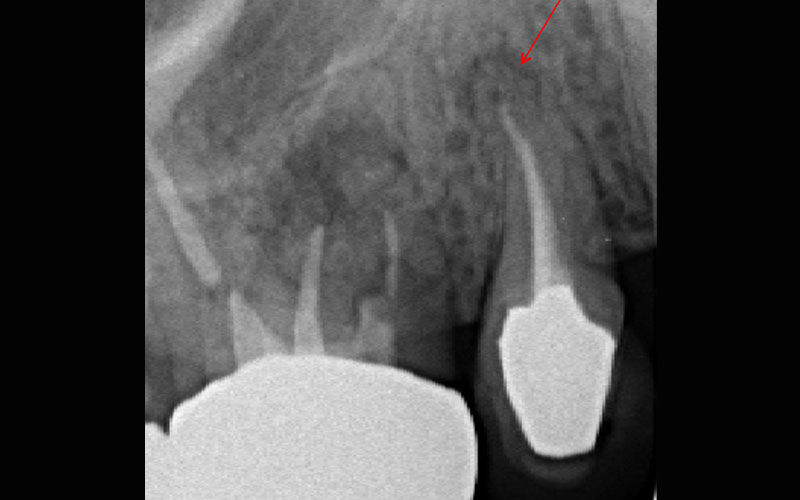

白い部分はずっと昔に治療された防腐剤ですが、根っこの先っぽまで届いていません。また、根っこの先っぽには透過像がありインプラントに近接していました。 |

根管治療が終わった後のレントゲン写真です。根尖まで防腐剤が緊密に充填されていて、透過像も無くなっています。比較してみると、 |

|---|

この様に透過像が無くなり防腐剤も適切な位置に詰められていることがわかります。 |